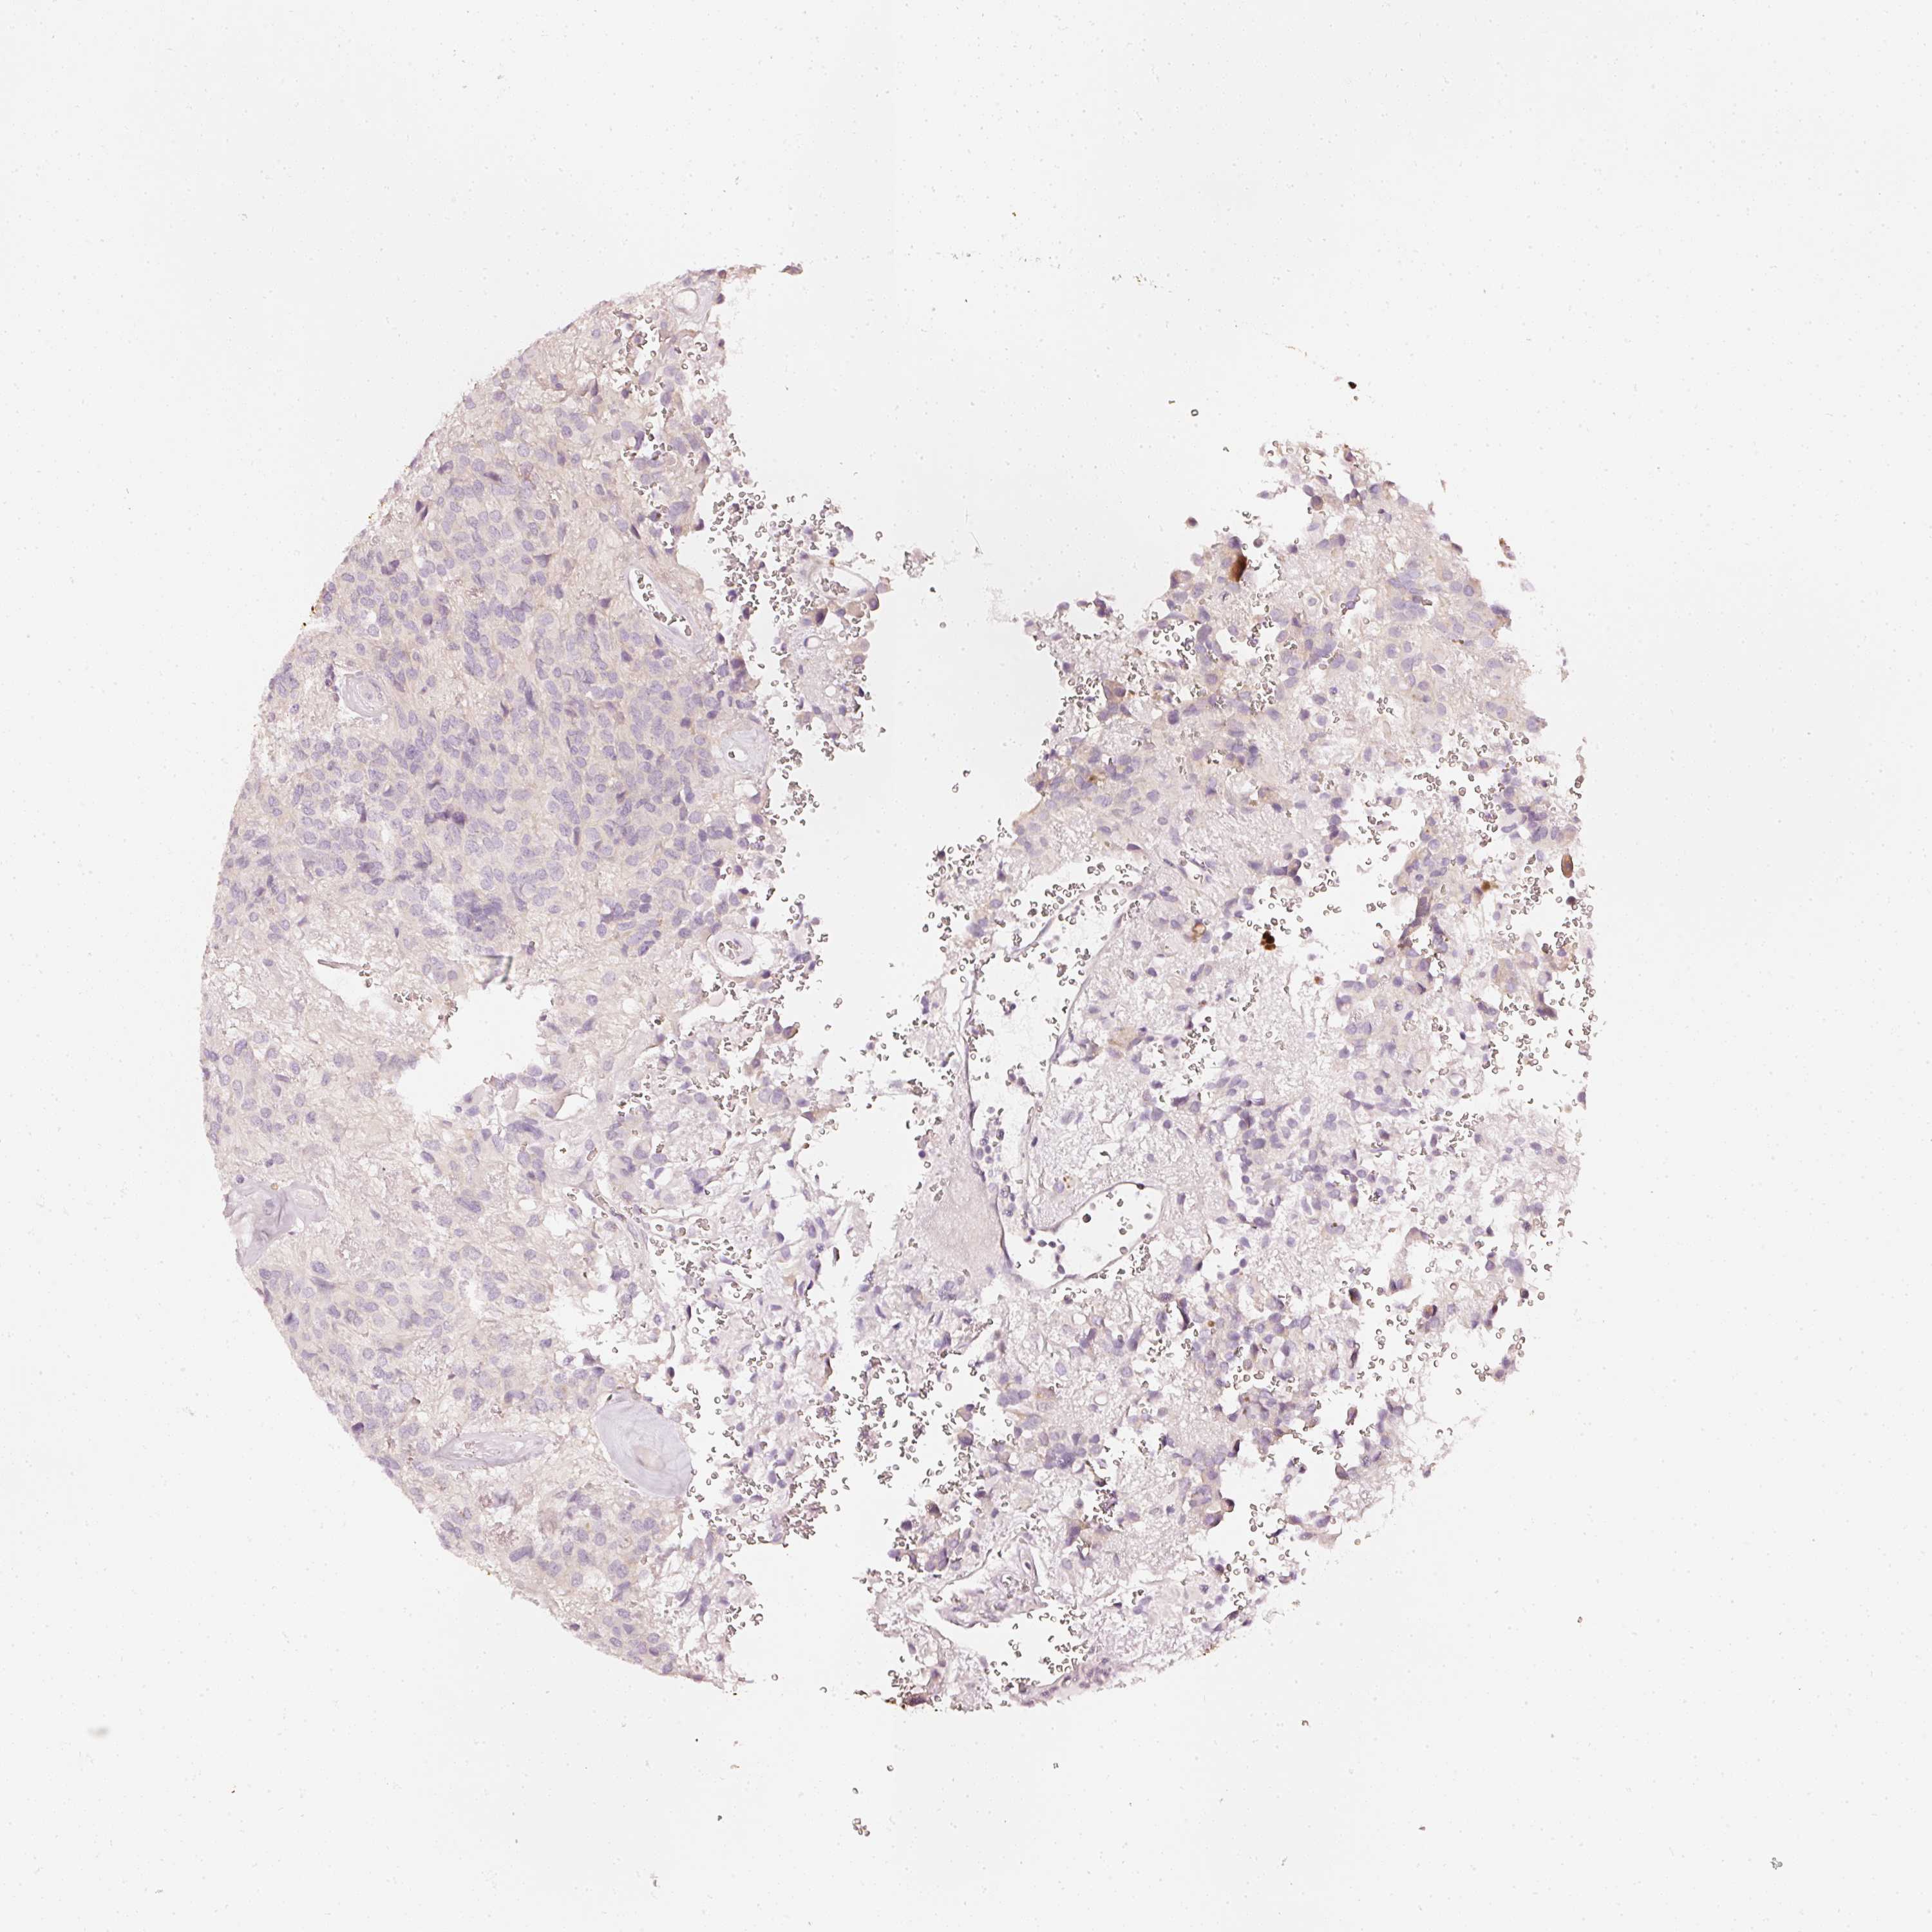

GLIOMA - Protein expressioni

A mouse-over function shows sample information and annotation data. Click on an image to view it in a full screen mode. Samples can be filtered based on level of antibody staining by selecting one or several of the following categories: high, medium, low and not detected. The assay and annotation is described here.

Note that samples used for immunohistochemistry by the Human Protein Atlas do not correspond to samples in the TCGA dataset.

Antibody stainingi

Antibody staining in the annotated cell types in the current human tissue is reported as not detected, low, medium, or high, based on conventional immunohistochemistry profiling in selected tissues. This score is based on the combination of the staining intensity and fraction of stained cells.

Each image is clickable and will lead to virtual microscopy that enables deeper exploration of all samples and also displays staining intensity scores, fraction scores and subcellular localization as well as patient and tissue information for each sample.

HPA023266

HPA023278

HPA023280

HPA023338

CAB002672

Glioma, malignant, High grade

Glioma, malignant, Low grade